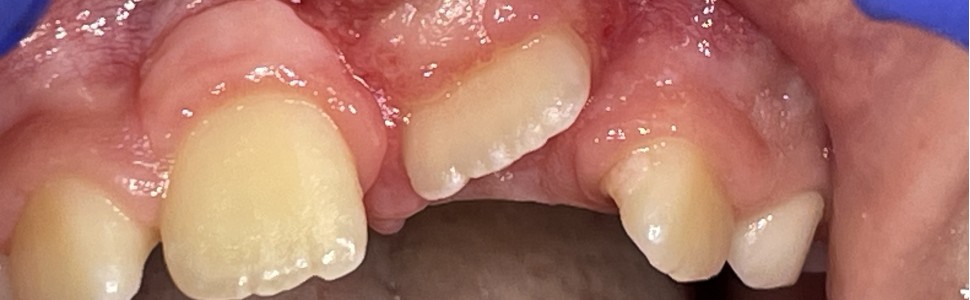

W artykule przedstawiono przypadek małoletniej pacjentki ortodontycznej, u której zastosowano jedną z procedur chirurgii śluzówkowo-dziąsłowej interceptywnej, aby na wczesnym etapie wyeliminować nieprawidłowości w przyzębiu. W aspekcie wargowym częściowo zatrzymanych górnych zębów siecznych przyśrodkowych wykonano dowierzchołkowe przesunięcie płata. W wyniku zabiegu uzyskano pożądany wymiar tkanki zrogowaciałej, tym samym zredukowano ryzyko rozwoju recesji dziąsłowych podczas dalszego leczenia ortodontycznego.

This article presents the case of a young orthodontic patient who underwent mucogingival interceptive surgery to correct early-stage periodontal abnormalities. An apically positioned flap was performed on the labial aspect of the partially impacted upper central incisors. The procedure achieved the desired dimension of keratinized tissue, reducing the risk of gingival recession during further orthodontic treatment.